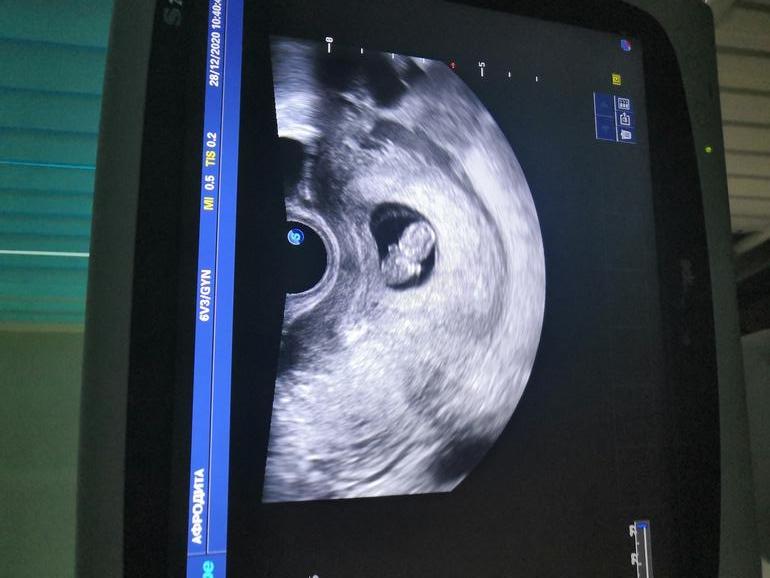

Теперь спокойна, можно ехать к маме на НГ🥰спасибо малыш, что закрепился по задней стенке, есть надежда на небольшой живот 😅